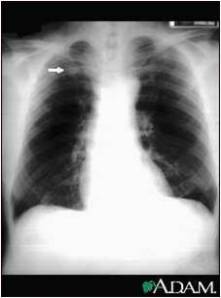

The following are examples of how Active TB may look on CXR:

Primary TB – LLL Infiltrate.

Mimics any pneumonia; occurs in debilitated pts, when Mtb first enters lung, and innate immune system unable to contain it.